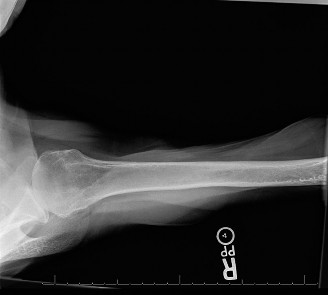

The correct answer is (C). This patient has an inferior shoulder dislocation (luxatio erecta) as seen in Figure 2–40. This is a very rare type of dislocation, which represents 0.5% of all dislocations. It carries the greatest risk of having an associated neurovascular injury, with the axillary nerve being the most frequently injured structure. Patients present with the shoulder locked overhead in full abduction. Closed reduction is generally successful and a subsequent MRI may be needed to assess for soft tissue injuries.

#### Figure 2–40 Luxatio erecta. Objectives: Did you learn...? To recognize the clinical presentation and physical examination findings associated with posterior GH instability?